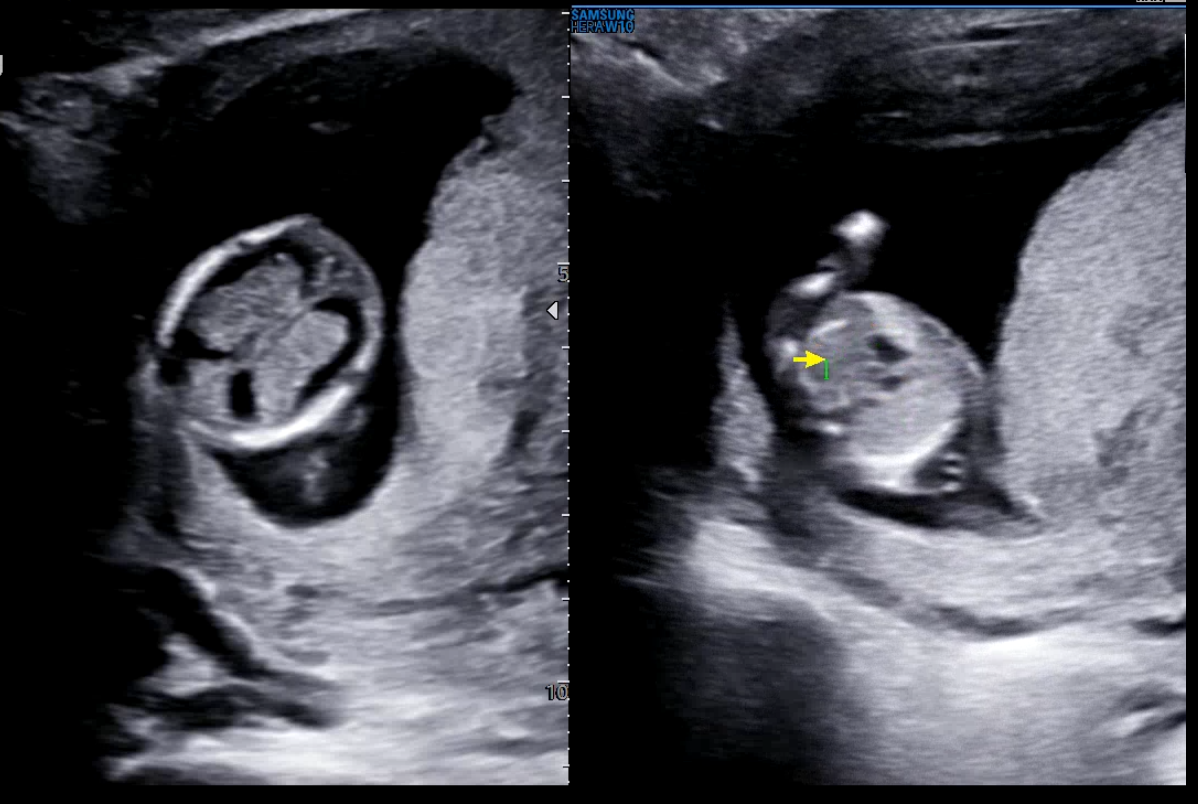

목둘레 투명대도 쟀는데 정상이였다. 정상치가 3mm 이하인데 3mm가 넘으면 다운증후군등의 선천성기형이 의심된다고 한다. (물론 이것만으로 결정되는건 아니고 후속되는 여러가지 검사까지 합쳐서 판별을 해야된다고 하니 저게 크다고 무조건 기형인건 아닌 것 같다.)

뇌와 심장이 제대로 있는지도 보고 위장이 있는지도 확인했다.